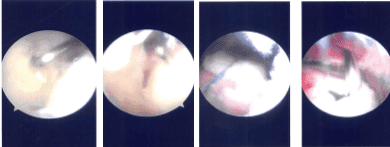

Intraoperative Arthroscopy Images